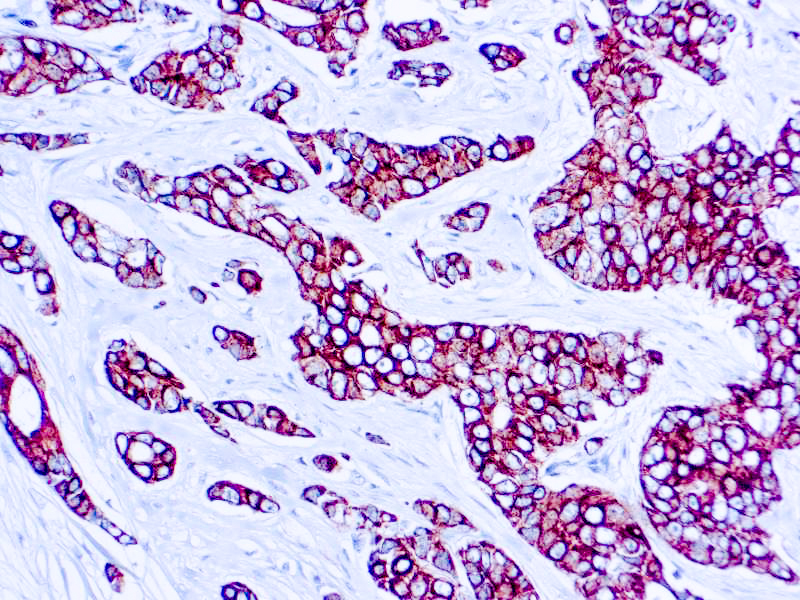

Cytokeratin (CAM5.2)

Anti-Cytokeratin (CAM 5.2) reagent has a primary reactivity with human keratin proteins that correspond to Moll’s peptides #7 and #8, Mr 48 and 52 kilodaltons (kd), respectively. Cytokeratin 7 and 8 are present on secretory epithelia of normal human tissue but not onstratified squamous epithelium. Anti-Cytokeratin (CAM 5.2) stains most epithelial-derived tissue, including liver, renal tubular epithelium, and hepatocellular and renal cell carcinomas. Anti-Cytokeratin (CAM 5.2) might not react with some squamous cell carcinomas.

| Positive Control Tissue | Colon, Lung, prostate and breast tissue. |